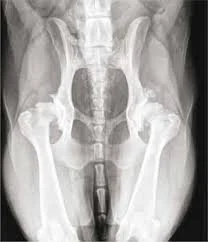

hip dysplasia dog dr hart

Some pets still want to be part of the family but struggle physically every time they try to move.

Many owners think these are simply age-related changes. Often they are signs of pain, especially arthritis or chronic orthopedic disease.

A pet does not have to cry out to be uncomfortable.

Arthritis in Older Dogs